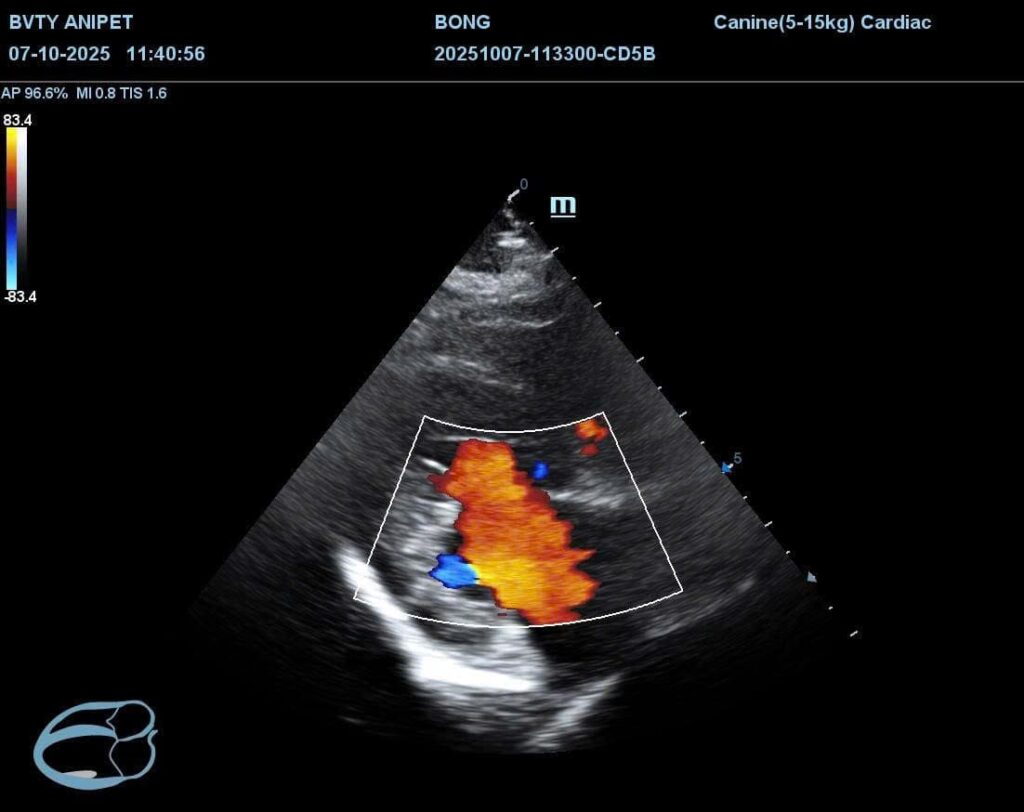

Siêu âm tim và chụp X-quang

Tiếp đến, bác sĩ sẽ tiến hành siêu âm tim và chụp X-quang tim phổi nhằm đánh giá cấu trúc tim, độ dày thành tim và tình trạng phổi. Siêu âm tim giúp quan sát trực tiếp sự co bóp của tim, trong khi X-quang cho biết tim có bị phì đại hay dịch có ứ đọng ở phổi không.

Hai phương pháp này hỗ trợ phát hiện sớm các bệnh lý như suy tim sung huyết hoặc bệnh van tim ở chó mèo.